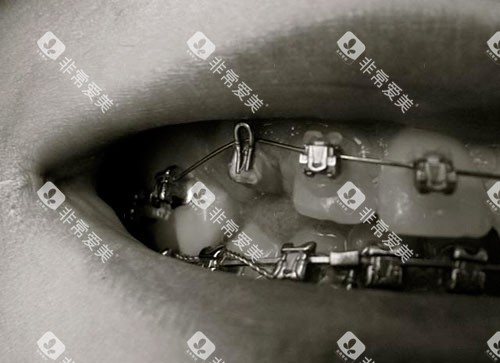

说起金属托槽矫正,那可是正畸界的“老炮儿”了。这种矫正方式历史悠久,技术成熟,价格也相对亲民。在北京,金属托槽矫正的价格一般在1万到2.5万元之间,具体还得看你的牙齿情况和所选医院。

金属托槽矫正的优点可不少。首先,它价格实惠,适合预算有限的朋友。其次,技术成熟,矫正结果可靠。不过呢,金属托槽矫正也有个小缺点,就是外观上金属托槽比较明显,可能会影响美观。但如果你更看重矫正结果和性价比,那金属托槽矫正肯定是个不错的选择。

如果你既想矫正牙齿,又不想让托槽太显眼,那陶瓷托槽矫正或许能满足你的需求。陶瓷托槽的颜色接近牙齿本色,相对不那么明显,能在一定程度上提升美观度。

在北京,陶瓷托槽矫正的价格一般在2万到3.5万元之间。虽然比金属托槽矫正贵一些,但考虑到它的美观性,这个价格还是物有所值的。不过呢,陶瓷托槽相对较脆,使用过程中需要更加小心,避免磕碰。